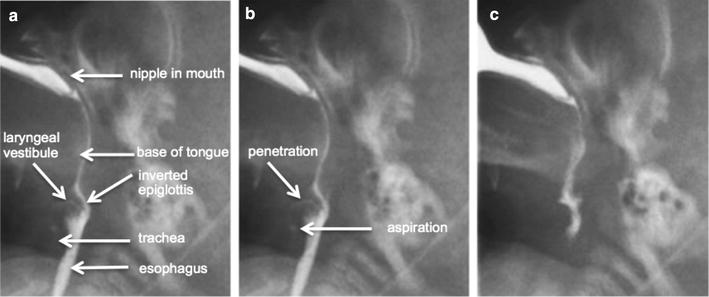

Video Swallow Study Aspiration

Initial Video Fluoroscopic Swallowing Study Shows Aspir

A The First Videofluoroscopic Swallow Study Vfss Pe

Figure 3 Usefulness Of Videofluoroscopic Swallow Study